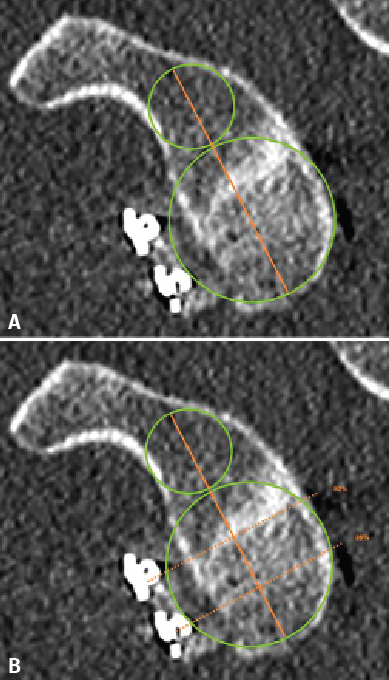

Figure 1. Estimation of glenoid axis and height according to the method of Barth(13). Two circumferences are traced: one lower, taking the posteroinferior glenoid border as reference, and one higher than the other and tangential to the glenoid borders. The line joining the centre of both circumferences is taken to represent the axis of the glenoid cavity. Over this, the height corresponding to half of the glenoid cavity and to 25% is established.

Taking the posteroinferior glenoid border as reference, we traced a first circumference over its contour, and a second circumference above the previous one and tangential to the glenoid borders. The line joining the centre of both circumferences was taken to represent the axis of the glenoid cavity. Over this we estimated the point corresponding to the half and 25% of the glenoid height (Figure 1). The sagittal section was used to determine the position of the graft in the craniocaudal direction (Figure 2). The length (in mm) of the bone defect was measured (B), along with the amount of bone graft covering the defect (A). Percentage covering of the bone defect was estimated from the ratio between A and B. The graft was considered to be well positioned when the percentage coverage of the defect was at least 90%.